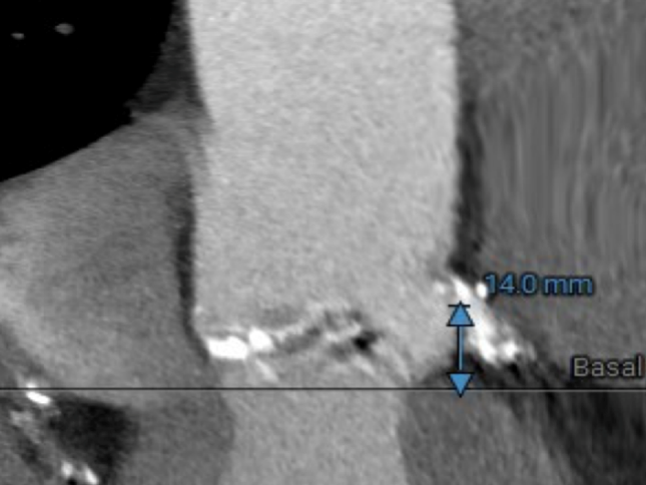

冠脉高度测量

LEFT CORONARY

左冠开口高度14.0mm